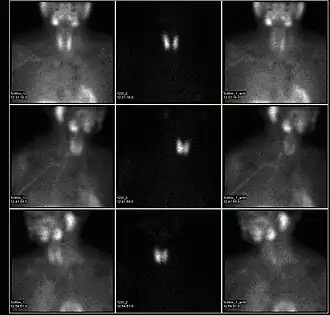

A nuclear medicine parathyroid scan demonstrates a parathyroid adenoma adjacent to the left inferior pole of the thyroid gland. The above study was performed with Technetium-Sestamibi (1st column) and Iodine-123 (2nd column) simultaneous imaging and the subtraction technique (3rd column).

A sestamibi parathyroid scan is a procedure in nuclear medicine which is performed to localize parathyroid adenoma, which causes Hyperparathyroidism.[1] Adequate localization of parathyroid adenoma allows the surgeon to use a minimally invasive surgical approach.

Imaging is not as reliable in patients with multiglandular parathyroid disease. In addition, size limitation of the abnormal gland can limit the detection by radionuclide scanning. SPECT (three-dimensional) imaging, as an adjunct to planar methods, may increase sensitivity and accuracy,[2] especially in cases of small parathymic adenomas. By using a gamma camera in nuclear medicine, the radiologist is able to determine if one of the four parathyroid glands is hyperfunctioning, if that is the cause of the hyperparathyroidism. Theoretically, the hyperfunctioning parathyroid gland will take up more of the Tc99m-sestamibi, and will show up 'brighter' than the other normal parathyroid glands on the gamma camera pictures, especially because of the internal biofeedback loop within the body with calcium inherently feeding back to calcium-receptors and inhibiting parathyroid hormone production within the normal parathyroid glands. Sometimes this determination must be made three or four hours later when activity taken up by the thyroid and normal parathyroid glands fade away; the abnormal parathyroid gland retains its activity, while the radiopharmaceutical is eluted out of the normal thyroid gland. In patients with nodular goiter or functional tumors of the thyroid gland, increased uptake of the sestamibi agent is possible and makes parathyroid localization difficult or confusing.